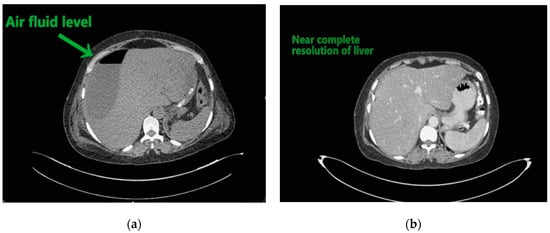

Radiographic investigations revealed large air fluid level under the right diaphragm with multiple air fluid levels in the right upper part of the abdomen (Figure 1a,b).

Contemplating unusual location of air fluid level in an otherwise stable patient, contrast enhanced computed tomography (CECT) of the abdomen and pelvis was done. CECT was suggestive of liver abscess in segment VII, VI which was 300 cc liquified with gas formation within. The abscess had ruptured with collection tracking along the right paracolic gutter till pelvis with 800 cc liquified large collection noted within (Figure 2a and Figure 3a).

The patient underwent ultrasound guided percutaneous abscess drainage and placement of 12-Fr and 14-Fr catheter in liver and pelvic collections respectively. The aspirate was purulent and Klebsiella pneumoniae was detected in cultures. Blood culture was negative even on repeated samples. Gene xpert (CB NAAT) was negative for mycobacterium tuberculosis (MTB). Fluid samples were also negative for malignant cells. She was started on antibiotics Piperacillin and tazobactum combination and monitored for blood glucose levels as a high suspicion of diabetes. Antibiotics was switched to imipenem as per the sensitivity of fluid cultures. She was tested negative for human immunodeficiency virus (HIV). Conservative management was continued as the patient improved with a repeat CECT after 10 days showing complete resolution of liver abscess and 30–40 cc residual collection in pelvis. Her liver enzymes became normal. Drains were removed on day 12 and day 14 from liver and pelvis respectively. She developed an induration of 13 mm when tested for tuberculin skin antigen test at 72 h post inoculation suggesting positive test. Fluid adenosine deaminase (ADA) levels were found to be 250.5 U/L and patient started on category 1 anti-tubercular treatment. Patient was discharged on day 15 without sequelae.

Figure 2. (a) Liver abscess showing air fluid levels; (b) showing resolution after 10 days.